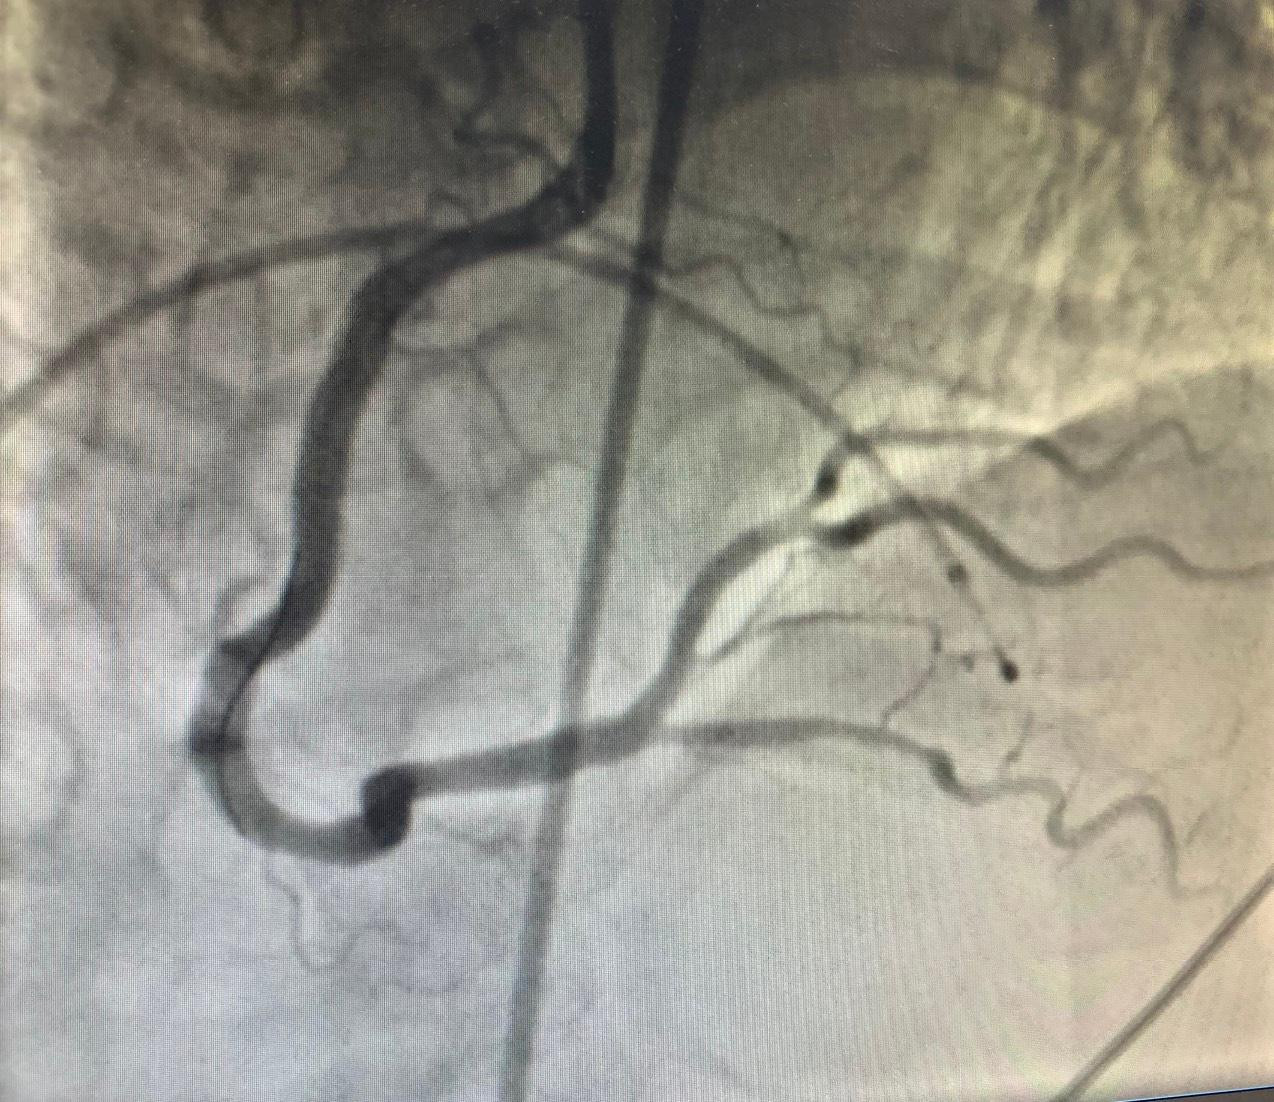

| Mạch vành của bệnh nhân (hình trên) bị tắc nghẽn trước can thiệp và được tái thông sau can thiệp (hình dưới) |

Thế nhưng, tình trạng rung thất của người bệnh vẫn lặp đi lặp lại. “Nếu chờ cho bệnh nhân ổn định mới can thiệp thì chúng tôi không có cơ hội. Với quyết tâm cứu bệnh nhân, ê kíp liên chuyên khoa đã quyết định vừa sốc điện chuyển nhịp để xử lý tình trạng rung thất đồng thời vừa can thiệp đặt stent cho bệnh nhân. Sau hơn 5 phút chạy đua với tử thần, tổng cộng hơn 30 lần sốc điện, chúng tôi đã can thiệp thành công mạch vành, đặt 1 stent tái thông vị trí mạch máu bị tắc tạm thời giúp người bệnh qua được nguy kịch” – PGS.BS Nguyễn Văn Tân cho hay.

Theo PGS.BS Nguyễn Văn Tân, thực tế can thiệp mạch vành cho thấy, bệnh nhân tổn thương cả 2 nhánh, trong đó nhánh bên phải tắc hoàn toàn đoạn gần (RCA) do huyết khối. Tuy nhiên, sau can thiệp, bệnh nhân tiếp tục bị nhịp nhanh thất, rung thất. Các bác sĩ đã tiếp tục sốc điện, đồng thời sử dụng thuốc, bổ sung điện giải giúp bệnh nhân phục hồi dần.

Sau 24 giờ can thiệp, bệnh nhân đã hoàn toàn tỉnh táo, tiếp xúc tốt, ăn uống được.